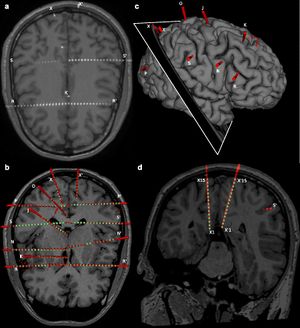

- 1.81 SEEG Assistant: A 3D Slicer Extension to Support Epilepsy Surgery

Publication: Front Neurosci. 2017 Oct 9;11:554. PMID: 29062268 | PDF Authors: Behan B, Chen DQ, Sammartino F, DeSouza DD, Wharton-Shukster E, Hodaie M. Institution: Division of Brain, Imaging and Behaviour - Systems Neuroscience, Krembil Institute, University Health Network, Toronto, ON, Canada. Abstract: Diffusion-weighted imaging (DWI)-based tractography has gained increasing popularity as a method for detailed visualization of white matter (WM) tracts. Different imaging techniques, and more novel, advanced imaging methods provide significant WM structural detail. While there has been greater focus on improving tract visualization for larger WM pathways, the relative value of each method for cranial nerve reconstruction and how this methodology can assist surgical decision-making is still understudied. Images from 10 patients with posterior fossa tumors (4 male, mean age: 63.5), affecting either the trigeminal nerve (CN V) or the facial/vestibular complex (CN VII/VIII), were employed. Three distinct reconstruction methods [two tensor-based methods: single diffusion tensor tractography (SDT) 3D Slicer, eXtended streamline tractography (XST), and one fiber orientation distribution (FOD)-based method: streamline tractography using constrained spherical deconvolution (CSD)-derived estimates (MRtrix3)], were compared to determine which of these was best suited for use in a neurosurgical setting in terms of processing speed, anatomical accuracy, and accurate depiction of the relationship between the tumor and affected CN. Computation of the tensor map was faster when compared to the implementation of CSD to provide estimates of FOD. Both XST and CSD-based reconstruction methods tended to give more detailed representations of the projections of CN V and CN VII/VIII compared to SDT. These reconstruction methods were able to more accurately delineate the course of CN V and CN VII/VIII, differentiate CN V from the cerebellar peduncle, and delineate compression of CN VII/VIII in situations where SDT could not. However, CSD-based reconstruction methods tended to generate more invalid streamlines. XST offers the best combination of anatomical accuracy and speed of reconstruction of cranial nerves within this patient population. Given the possible anatomical limitations of single tensor models, supplementation with more advanced tensor-based reconstruction methods might be beneficial. |

Reconstruction methods differ in how they represent underlying diffusion processes. (1) Axial view of a sample tensor map displaying CN V entry into the brainstem, (2) Tensors visible as glyphs displaying CN V entry into the brainstem, (3) results from single diffusion tensor tractography (SDT) after placing region-of-interest (ROI) seeds on anterior portions of CN V bilaterally. Generated streamlines do not show their projections to brainstem nuclei, (4) results from EXtended Streamline Tractography (XST) after placing ROI seeds on anterior portions of CN V bilaterally. Streamlines projecting to the area of the nuclei of the trigeminal nerves can be seen, (5) Axial view of sample fiber orientation distribution (FOD) map displaying CN V entry into the brainstem, (6) results from streamline tractography on FODs derived from constrained spherical deconvolution (CSD) after placing ROI seeds on anterior portions of CN V bilaterally. Streamlines projecting to the area of the nuclei of the trigeminal nerves can be seen. |